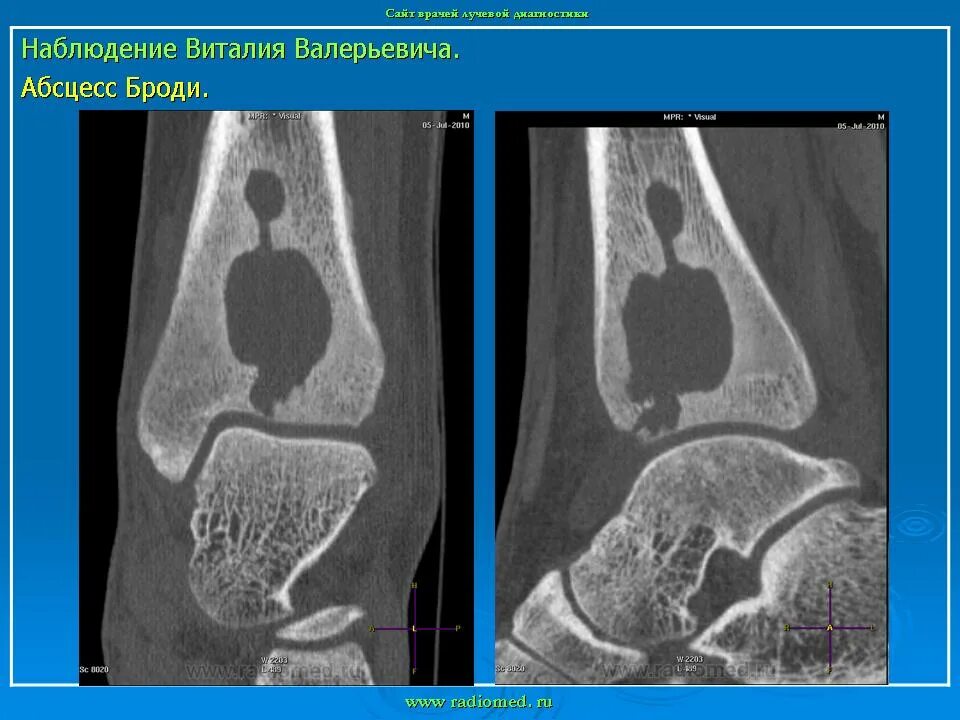

Кт тканей